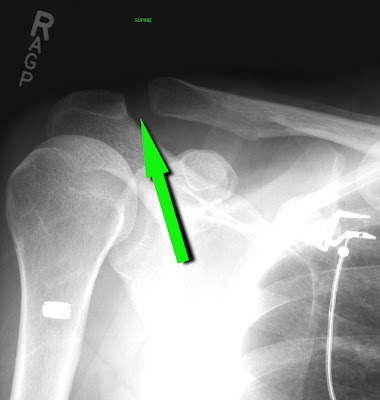

Two hours, a trip to the ER in an ambulance on a backboard and some X-rays later, I had a diagnosis:

You see that space between those two bones?  That's not supposed to be there.

After reviewing my films, the ER doc came into my room and said "Good news - nothing is broken!"  Still flat on my back with a neck brace on, my teeth gnashed together with pain, I whispered, "I beg to differ."  He ignored me.  "We'll get you in a sling and you can get out of here!"  Hang on, I thought.  There is the small matter of me getting to wallow in my misery a bit longer, and also - shouldn't an orthopedist probably review these films?  "Do you want something for the pain?" he asked as he removed my neck brace and propped up the hospital bed, a little quicker than I would have preferred, which caused my shoulder to erupt in pain that flowed like molten lava from a crack in the earth across my chest and down my arm.  "Does the Pope shit in the woods?" I thought (I was still a little dazed).  But, in reality, all I could get out was a pathetic "Uh-huh."